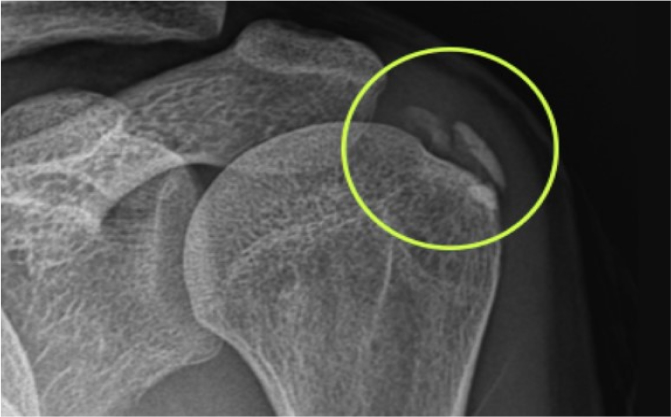

어깨에 특별한 충격이나 외상이 없었는데도

계속해서 통증이 느껴지시나요?

수면 도중 깰 정도의 통증을 느끼시나요?

어깨를 감싸고 있는 회전근개 힘줄에 칼슘

성분이 침착되면서 염증을 일으키는 질환입니다.

석회가 자리를 잡으면 자연흡수가 어렵기 때문에 조기 진단과 치료가 매우 중요합니다.